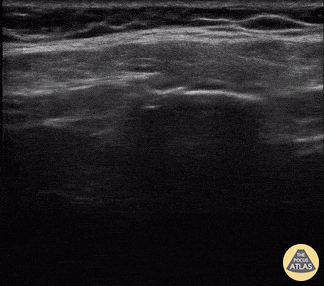

A middle aged man presented 1 week after sustaining a fall with direct injury to his left chest. He reported pain with inspiration and coughing; he localized pain to one specific area of his chest wall. Seen here is the image obtained when the linear probe was placed in the longitudinal plane to his area of point-tenderness. Notice the disruption of the hyperechoic cortex of the rib. Findings were confirmed in the transverse plan. The patient went on to have an anterior serratus nerve block for pain control related to his rib fracture. Mandy Peach, MD @mandy_peach Saint John Regional Hospital. NB, Canada